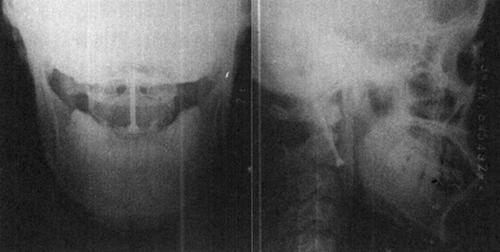

图13-23 48岁女性C1爆裂骨折,枕颈及C1~C2关节不稳。做后路枕颈固定,镶嵌植骨。枕骨用双皮质螺钉,C2为椎弓根钉